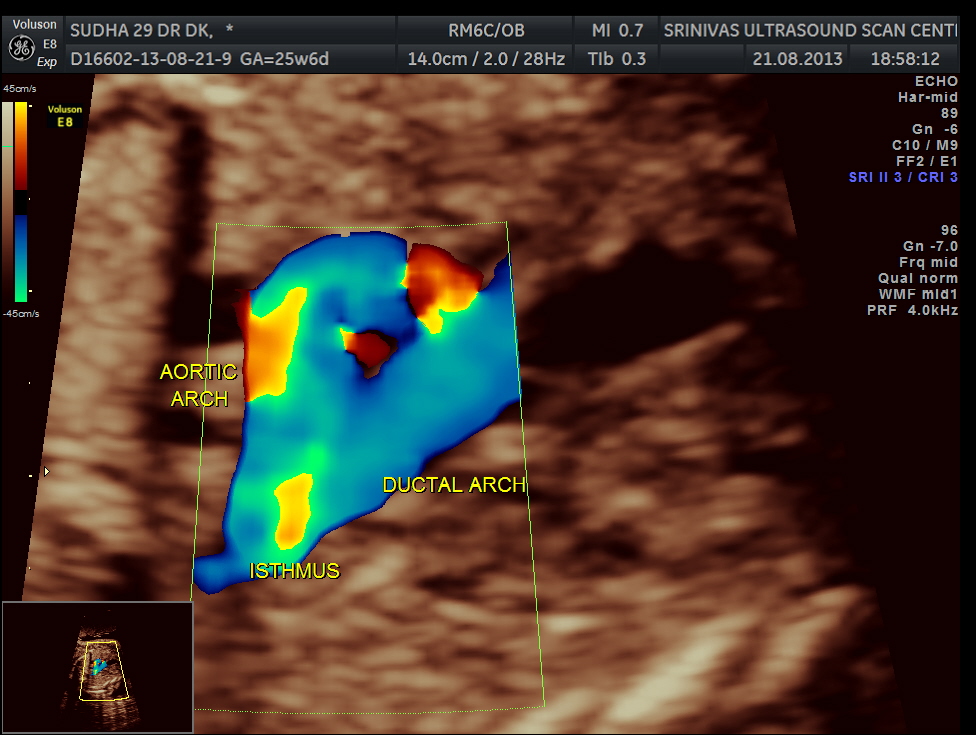

the following 3 D reconstructed image shows the parallel flow of the great arteries